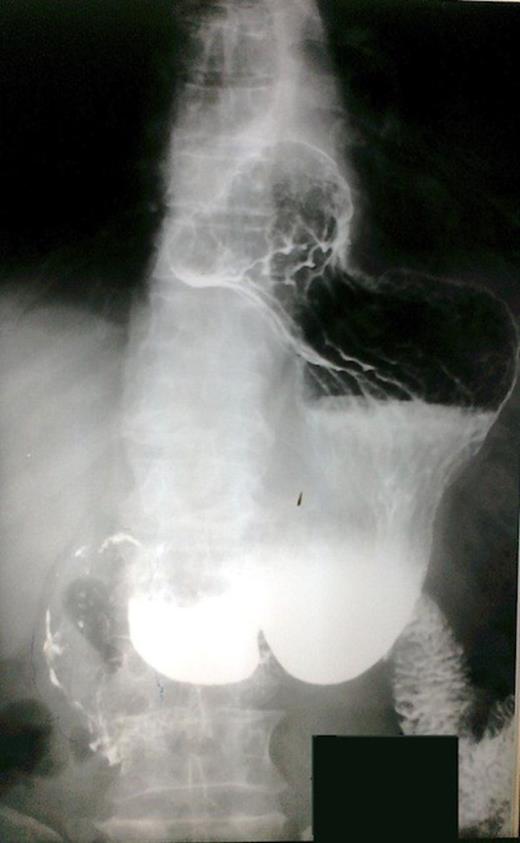

The patient underwent investigation with gastroscopy, where torsion of the bulb of the stomach was found. The insertion of the instrument via the pylorus was not impossible (Figure 1). The upper gastrointestinal series disclosed polypous masses in the bulb and the prepyloric part of the stomach (Figure 2). The computerized tomography (CT) scan was unremarkable. The magnetic resonance (MRI) scan showed an exophytic mass with disturbance of the plication of the intestinal lumen in the area of the pylorus and the duodenum. Also, few small hepatic cysts were found.

Esophagogastroduodenoscopic examination. Prolapsus and torsion of the bulb of the stomach.